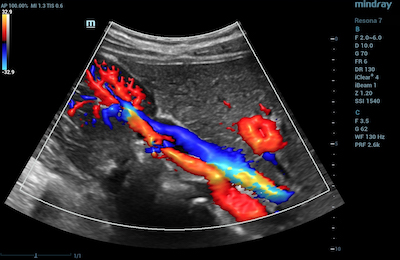

- Kidneys – CDI is used in renal ultrasonography to assess kidney issues such as renal hypertension, renal vein thrombosis, tumors, and hypovolemia – a condition that occurs from low blood volume.

Color Doppler Glazing Flow of Renal Color Doppler Ultra Micro Angiography of Artery and Vein